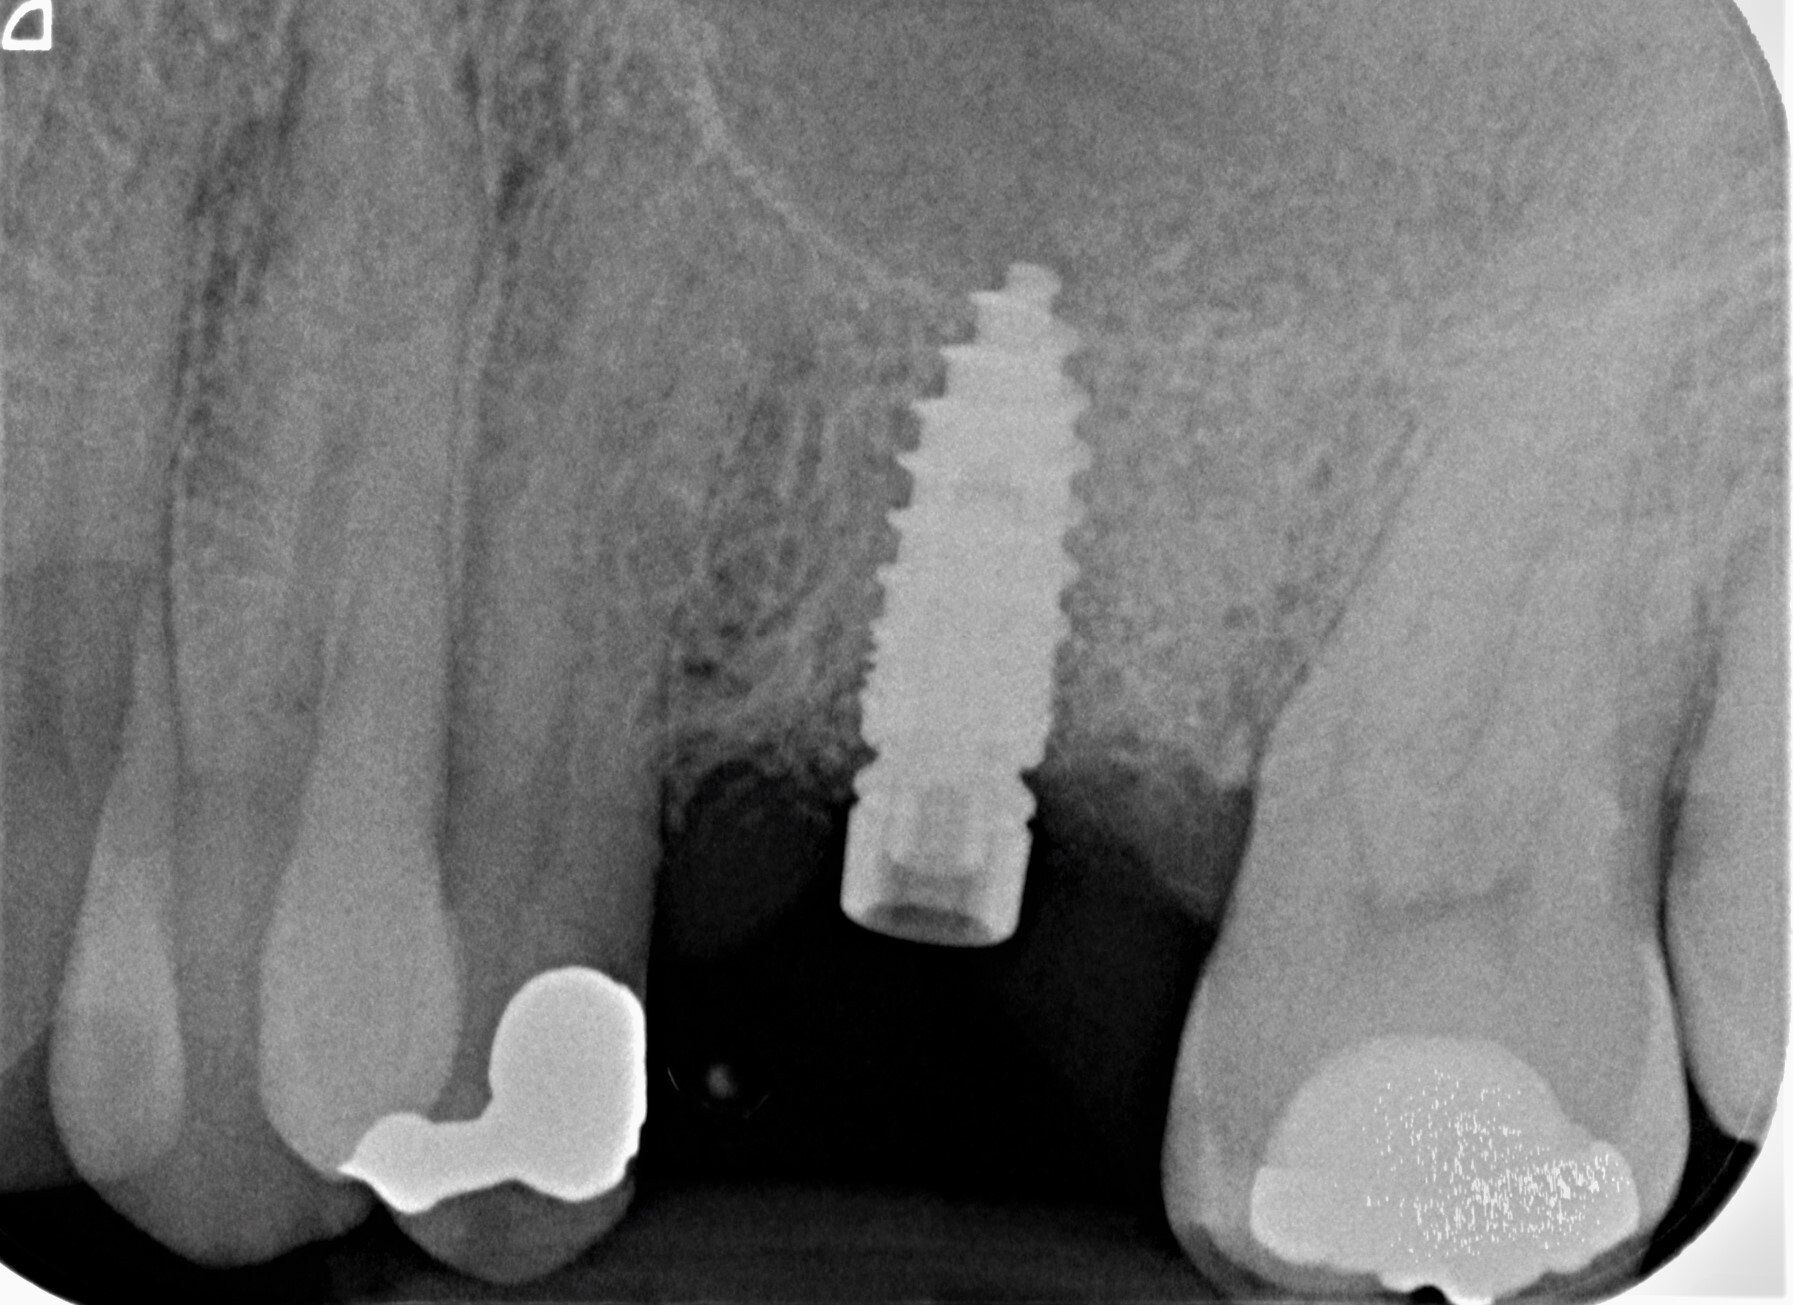

Durch den Verlust des Zahnes wandelt sich der Kieferknochen um. Nach der oberflächlichen Heilung wird das knöcherne Zahnfach vom Körper rasch abgebaut. Knochen ist für den Körper ein "teures" Gewebe, und ohne die funktionelle Kaubelastung durch einen Zahn gibt es für den Körper keinen Grund mehr, das knöcherne Zahnfach zu erhalten. Allein im ersten Jahr nach der Zahnentfernung gehen 50% des umgebenden Knochens verloren! Das ist insbesondere dann von Nachteil, wenn geplant ist, später ein Implantat für den Ersatz des Zahnes zu setzen. Ohne kiefererhaltende Maßnahmen reicht oftmals der nach der Heilung verbliebene Knochen nicht mehr aus, ein hinreichend großes Implantat einzusetzen bzw. dieses auch ideal zu positionieren.

Das Verfahren ist schonend und erfordert keinen zweiten Eingriff. Materialien tierischen Ursprungs werden vermieden. Die Aufbereitung findet direkt nach der Zahnentfernung in unserem Labor statt. Nach ca. 25 Minuten kann das Knochenfach aufgefüllt werden. Der Bereich muss für zwei Wochen geschont und auf der anderen Seite gekaut werden. Es sollte zwei Tage nicht geraucht werden. Alles weitere können wir den Selbstheilungskräften unsres Körpers überlassen.